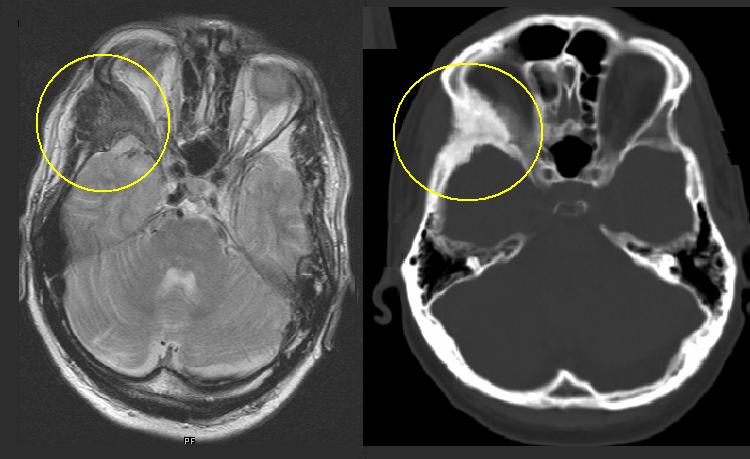

КТ анатомия сосцевидного отростка: особенности и показания